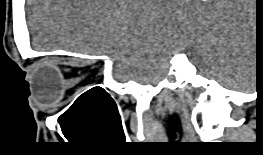

Орбиты (или глазницы) – это костные углубления в лицевом черепе, где расположены глазные яблоки, окруженные жировой клетчаткой, а также слезные железы, слезные каналы, сосуды, нервы, мышцы и связки глаза. Такая небольшая по объему область содержит важные анатомические структуры, обеспечивающие нормальную функцию органа зрения.

Кроме того, область орбиты тесно связана с близлежащими структурами – полостью черепа с расположенным в ней головным мозгом, а также с полостью носа, околоносовыми пазухами и носоглоткой. Различные патологические процессы могут развиваться как в самой глазнице, так и в околоорбитальных структурах, но при этом распространяться на область орбит.

Сложное строение глазницы и взаимосвязь с соседними анатомическими структурами затрудняет диагностику заболеваний глазного яблока и его придатков. Одним из наиболее информативных методов обследования органа зрения и окружающих тканей является мультиспиральная компьютерная томография. Кроме высокой информативности методика отличается быстротой и неинвазивностью (то есть не требует вмешательства в организм человека). Принцип получения изображений построен на применении ионизирующего излучения и разной способности тканей поглощать рентгеновские лучи.

Новейшее оборудование наших медицинских центров представлено современными мультиспиральными компьютерными томографами экспертного класса TOSHIBA AQUILION. Различные версии аппаратов способны выполнять одновременно 64 или 128 тончайших срезов исследуемой зоны. Таким образом получаются детальные изображения высокого качества за несколько секунд. Толщина срезов при этом составляет от 0,5 мм, что позволяет выявить патологические процессы на самых ранних стадиях развития, тем самым повысить шансы больного на успешное лечение.

На основе результатов сканирования аппараты выстраивают трехмерные модели органов и тканей, что дает возможность увидеть их точное пространственное расположение по отношению друг к другу.

Мультиспиральная компьютерная томография лучше всего визуализирует ткани с высокой плотностью, к которым, в частности, относится костная ткань. Это делает КТ незаменимой при диагностике травматических повреждений глазниц, а также для выявления инородных тел орбит.

В некоторых ситуациях для оценки состояния мягких тканей глазниц или структур глазных нервов, а также прилегающих к ним областей более предпочтительной является методика магнитно-резонансной томографии. В этих случаях врач направляет пациента на МРТ орбит. Данное исследование можно провести в условиях нашей клиники на новейшем высокопольном 32-канальном томографе экспертного уровня.